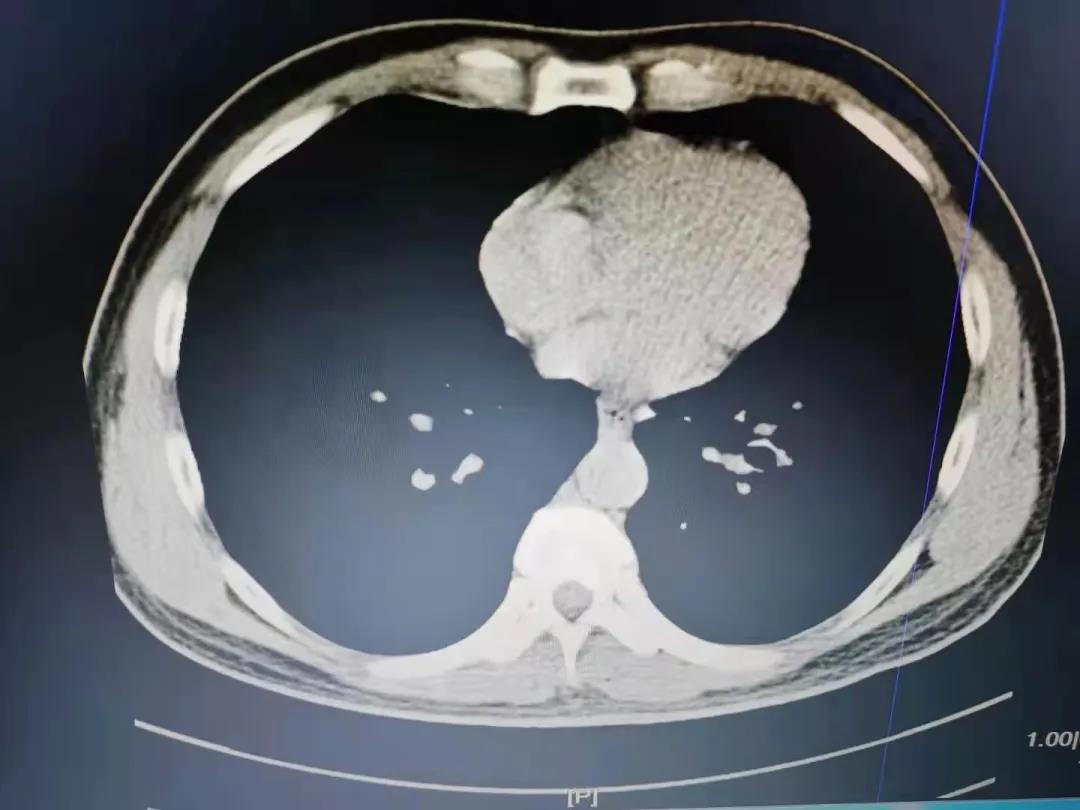

患者因“反复咳嗽1年余”就诊,查阅患者3年前的胸部CT片提示左下叶基底段高密度影,未予治疗。门诊完善胸部CT提示左下叶外后基底段支气管腔内异物并阻塞性肺炎。拟诊“1.支气管异物2.阻塞性肺炎”收入院,完善术前相关检查,排除支气管镜检查及治疗的禁忌症。考虑异物堵塞时间过长,有堵塞性肺不张,同时异物会刺激肉芽组织生长,经讨论后决定先行支气管镜检查。第一次进镜可见左下叶外后基底段支气管开口处大量的肉芽组织生长,触之易出血,异物完全被肉芽组织包裹,吸出大量粘稠分泌物,分泌物涂片见大量白细胞。考虑盲目取出异物,出血风险极高,决定抗炎1周后复查。